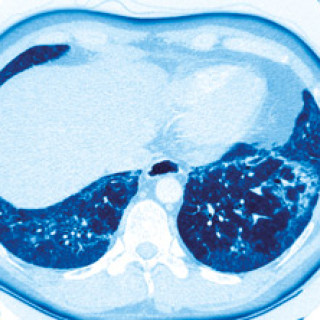

Insidensen av plutselig hjertedød under fysisk aktivitet hos yngre norske menn var 0,9 per 100 000. Vi har undersøkt forekomsten av plutselig hjertedød under fysisk aktivitet hos personer i alderen 15–34 år i årene 1990–97 (1). Det var 23 dødsfall (22 menn), dvs. gjennomsnittlig tre per år (1). Vi bygde på opplysninger fra dødsårsaksregisteret, dødsmeldinger og journaler. 22 ble obdusert. 11 døde av hjerteinfarkt, fem av myokarditt og to av ledningsforstyrrelser. Det var ett tilfelle av henholdsvis aortastenose, hjerteruptur, hypertrofisk obstruktiv kardiomyopati, koronararterieanomali og...